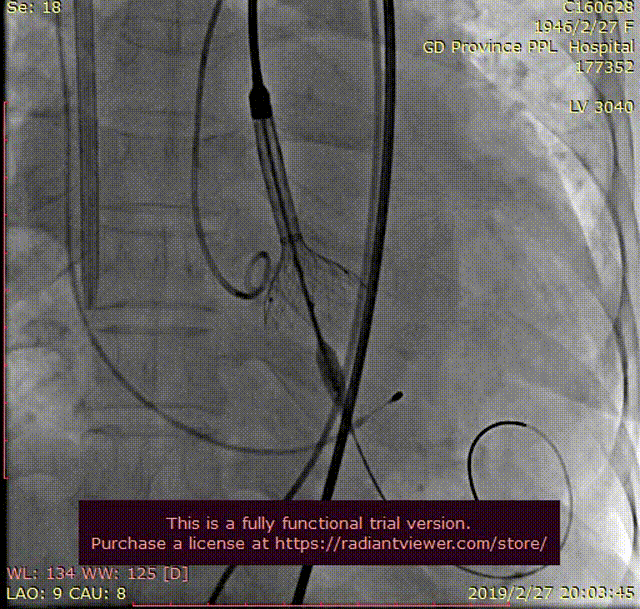

瓣膜释放前1/3

更换19F大鞘完成TAVR

双侧造影证实真腔DSA